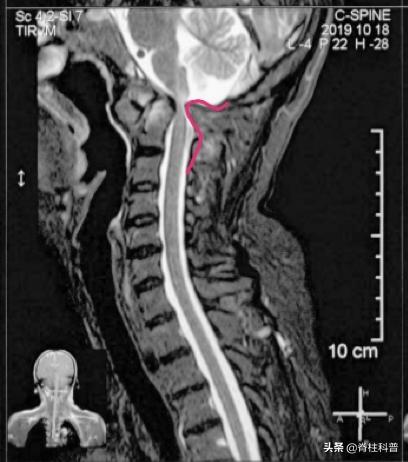

52岁女性患者3周前不慎从楼梯摔下后出现颈部疼痛、双上肢麻木乏力,以右上肢为重。

专科查体示:双上肢肌力三级,浅感觉减退,Hoffmann征(+),Babinski征(+)。

入院诊断为:

齿状突骨折伴寰枢椎脱位

颈脊髓不完全损伤

先天性寰枕融和

入院后立即行颅骨牵引,于10月21日在全麻下行后路颈椎管减压+寰枕融合+颈椎侧块螺钉内固定+髂骨取骨+神经根松解+硬脊膜修补术。

术后留置俩条引流管,其中颈部引流管于21日晚间发现引出液为淡红色血性液体,立即予引流瓶口抬高床面3cm。术后第一天引流液为淡红色血性液体370ml,第二天为195ml。